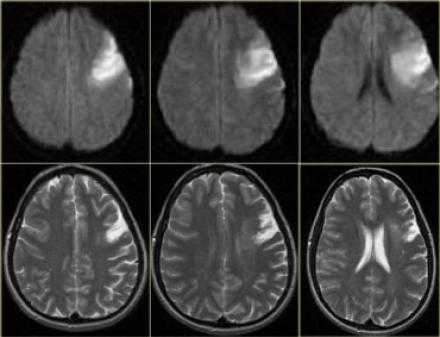

Диффузно-взвешенное изображение.

DWI наиболее чувствительна к инсульту. В результате цитотоксического отека возникает дисбаланс внеклеточной воды к Броуновскому движению, поэтому данные изменения выявляются отлично на DWI. В норме протоны воды диффундируют внеклеточно, поэтому теряется сигнал. Высокая интенсивность сигнала на DWI указывает на ограничение протонов воды диффундировать внеклеточно.

Представлены ДВИ инфаркт передней, задней, средней мозговой артерии.

Обратите внимание на изображение и предположите, где патология. После продолжите чтение. Вывод:

Есть некоторая гиподенсность и отек в левой лобной доли со старостью борозд в сравнении с контр-латеральной стороной. Далее DWI снимки того же пациента. После просмотра DWI нет сомнения, что это инфаркт. Именно поэтому DWI называют инсульт последовательностью.